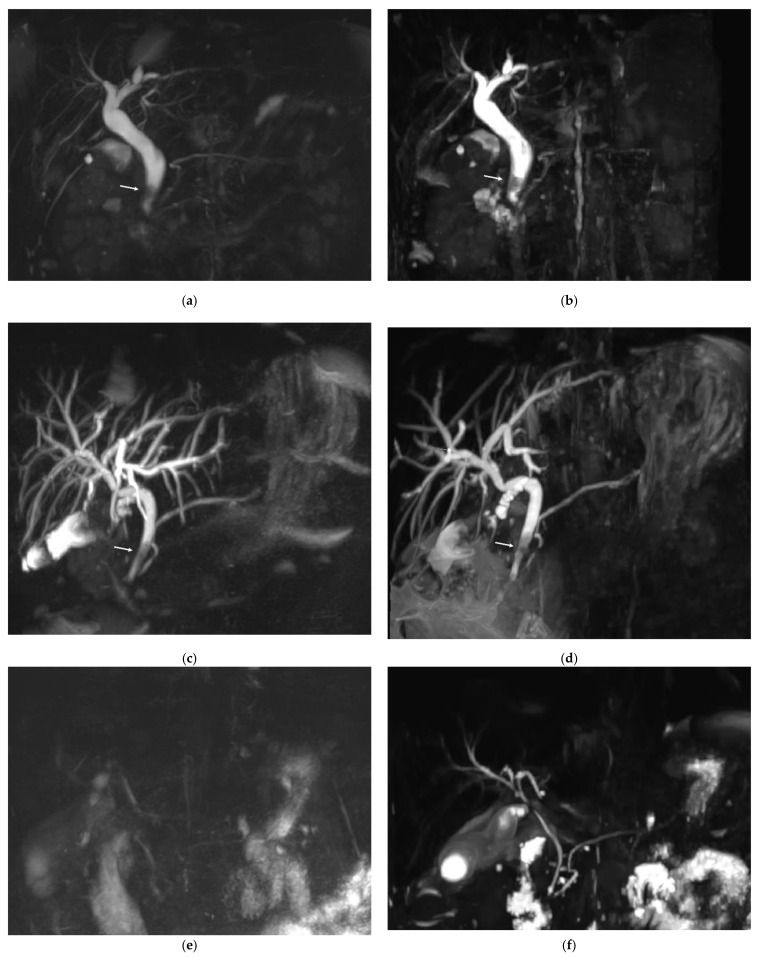

Based on the consensus between the two readers, CBD lithiasis was present in 10 of the 54 patients. In three patients, the calculi were visible on both MRCP sequences and on a non-MRCP sequence and confirmed by ERCP. In five patients, CBD lithiasis was visible on the RT-MRCP sequence and on a non-MRCP sequence but not on the CS-BH-MRCP sequence. Among these five patients, only one had calculi visible by ERCP and three had uninterpretable CS-BH-MRCP images (diagnostic confidence of 1). Finally, in two patients, calculi were visible on the CS-BH-MRCP sequence and on non-MRCP sequences but not on the RT-MRCP sequence. Among these two patients, only one had calculi visible by ERCP. The RT-MRCP was considered interpretable in both patients. No significant difference was found between the CS-BH-MRCT and RT-MRCP sequences for the detection of bile-duct lithiasis (p = 0.30). One stone was fortuitously discovered in one patient referred for BD-IPMN, only on CS-BH-MRCP sequence (not included in analysis). Figure 4 shows three examples of MRCP images of patients referred for suspected choledocholithiasis using RT-MRCP and CS-BH-MRCP sequences. Appendix A, Table A6 shows the number of CBD lithiasis detection based on the consensus between the two readers with each MRCP sequence and the agreement between the two sequences.